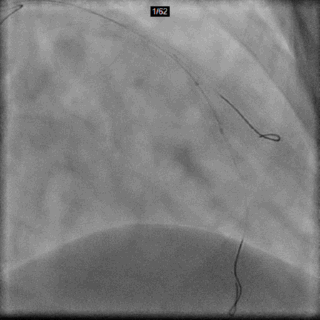

IVUS Co-registration

以IVUS探头位置记录下支架远端落脚点参考位置(无须“冒烟”)

Previous angiogram used as roadmap

IVUS测得LAD远端参考直径(media-media) = 3.65mm

以IVUS探头位置记录下支架近端落脚点参考位置(无须“冒烟”)

IVUS测得LAD近端参考直径(media-media) = 4.03mm

IVUS指导支架植入位置及尺寸

远端参考直径3.65mm

Distal to Proximal 17.61mm

近端参考直径4.03mm